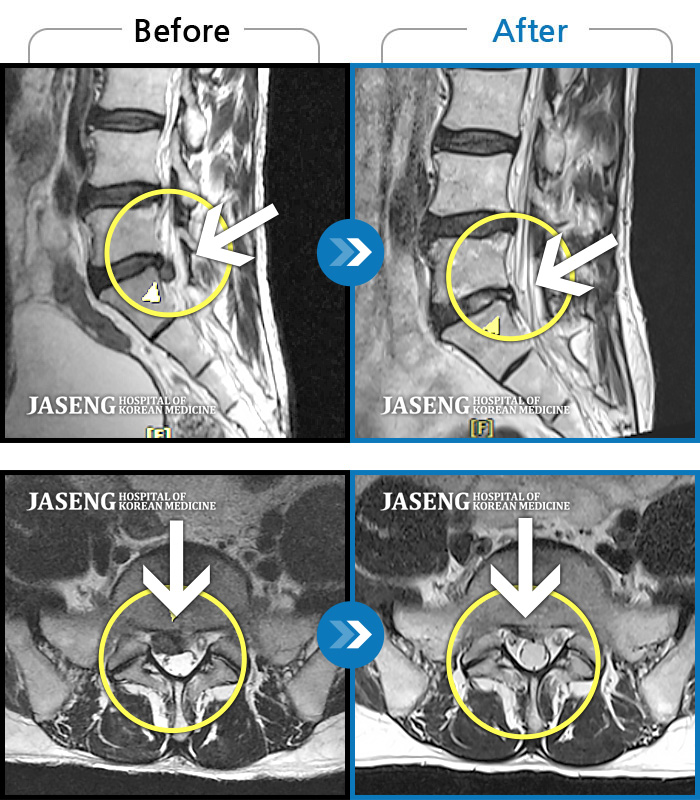

MRI 치료사례

허리 양측 통증, 서있을 때 찌르는 듯한 증상